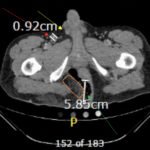

The computed tomography (CT) of the abdomen and pelvis revealed significant subcutaneous gas tracking along the perineum and right gluteal region (orange outline) into the scrotum with associated scrotal edema (yellow arrow) and subcutaneous inflammatory fat stranding of 0.92 cm (red arrow) consistent with Fournier’s gangrene. There is early fluid loculation along the right medial gluteal cleft of 5.85 cm (green arrow) without a sizeable drainable abscess seen.